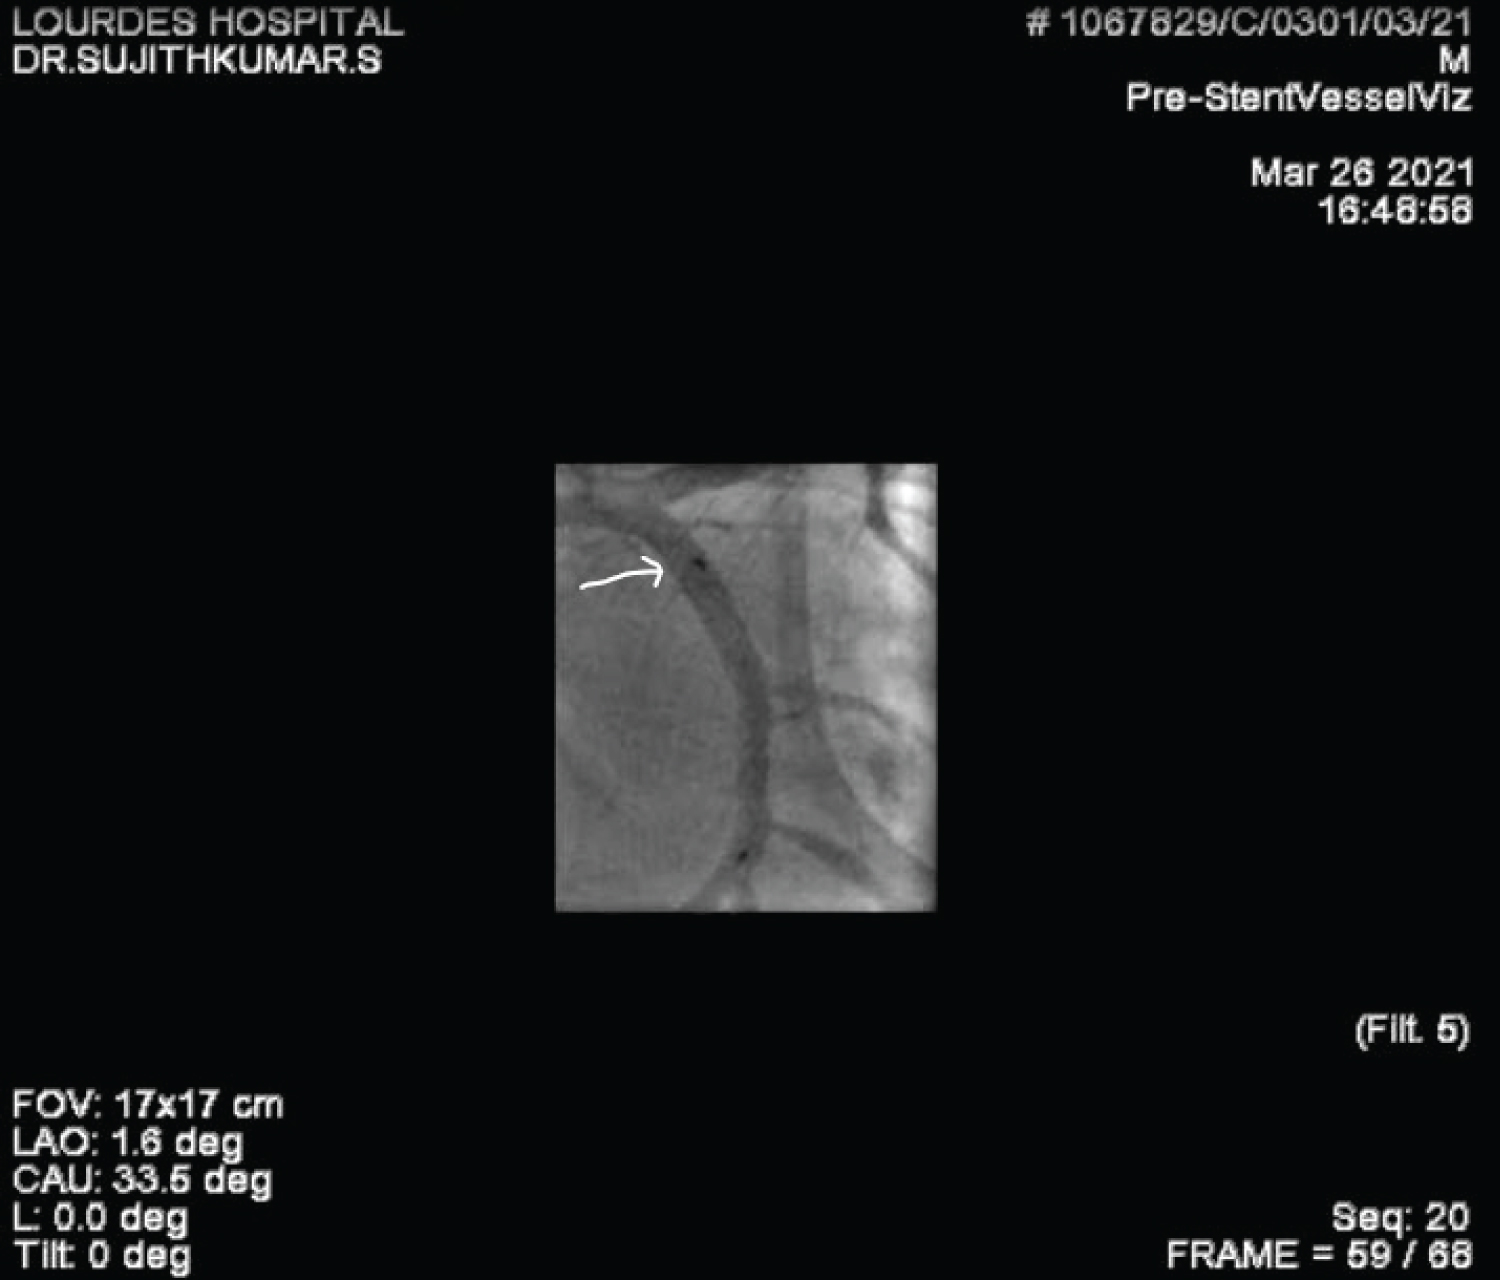

A 60-year-old gentleman was referred to our care with a diagnosis of Inferior Wall Myocardial Infarction, after receiving thrombolytic therapy at a local hospital. ECG, at admission, showed good ST resolution. He was taken up for elective coronary angiogram and revascularization. Coronary angiogram revealed a critical stenosis of dominant Left Circumflex artery (LCX) at Obtuse Marginal artery (OM2) (medina 1,0,1) with TIMI II flow distally (Figure 1 and Video 1). He underwent angioplasty and stenting with a single stent strategy. The LCX was predilated and was stented with a 3 × 24 mm Biomime stent at 14 atmospheres (Figure 2, Figure 3, Figure 4, Video 2 and Video 3). The OM2 was rewired and a dilatation of the ostial lesion of OM2 and kissing balloon inflation was done with excellent result. It was decided to do proximal optimization (POT) to the proximal stent with a 3.25 × 8 mm non-compliant (NC) balloon. But there was difficulty in tracking the balloon down into the stent and fluoroscopy showed a deformation of the proximal edge of the stent which was confirmed by the Stent Viz technology (Figure 5, Figure 6, Figure 7, Video 2 and Video 3). The same NC balloon was then used to post-dilate the stent and the proximal part of the stent was covered with another 3.5 × 13 mm biomime stent with excellent result (Figure 8). After 4 months follow up, the patient is asymptomatic and on dual antiplatelets.

Figure 1: Coronary angiogram in RAO Caudal projection showing critical stenosis of Left circumflex coronary artery and Obtuse marginal branch (medina 1,0,1). View Figure 1

Figure 4: Stent viz picture showing the stent after initial deployment - note the uniform spacing of the stent strut rings and normal shape of the stent. Note also the wire bias at the proximal edge of the stent. View Figure 4